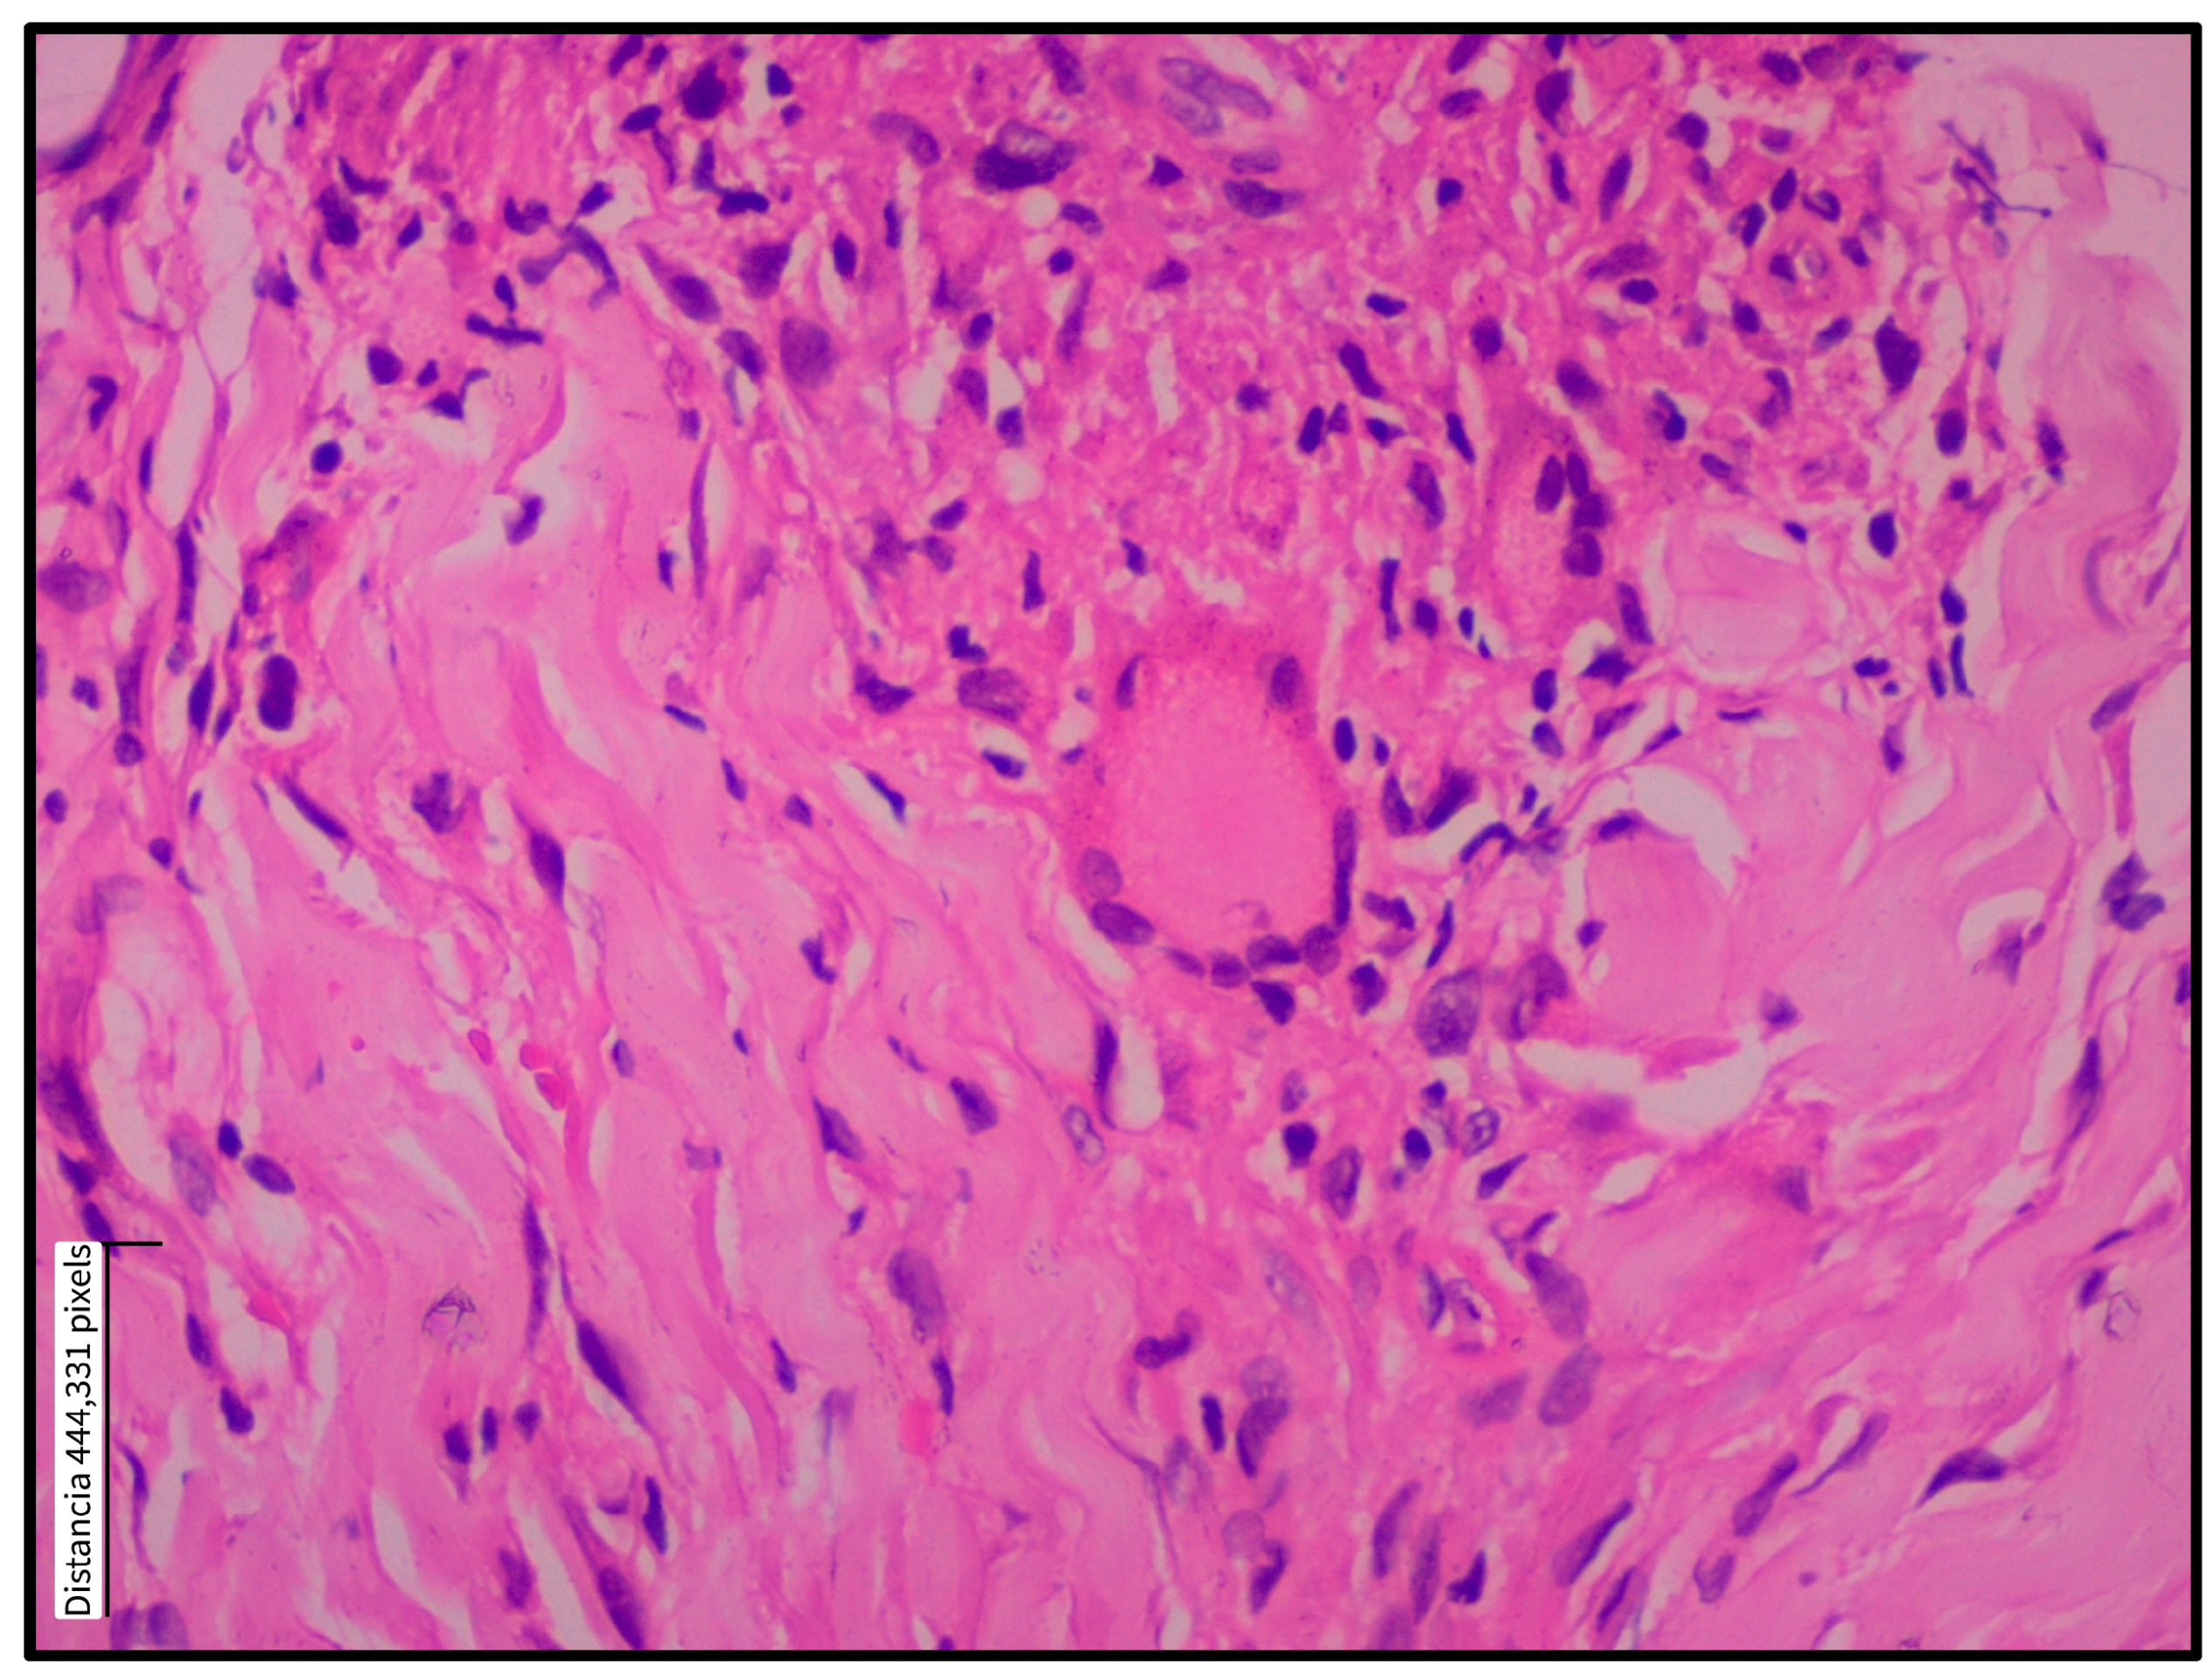

Figure 3.

Multinucleated giant cell within a dermal granuloma in cutaneous leishmaniasis. Multinucleated giant cell in the dermis of a skin biopsy from a patient with localized cutaneous leishmaniasis. A paraffin-embedded histological section stained with hematoxylin and eosin shows a multinucleated giant cell (center) surrounded by an inflammatory infiltrate composed predominantly of lymphocytes and histiocytes. Collagen bundles appear displaced by the cellular infiltrate. Magnification: 40×.